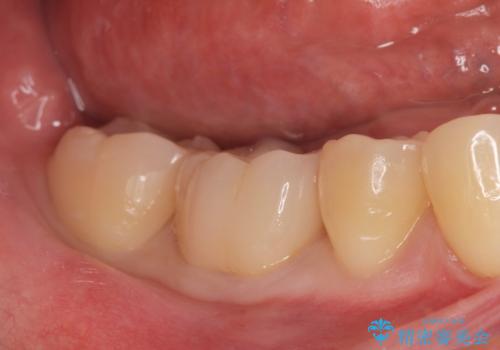

プラスチック樹脂は経年劣化して割れやすく、また虫歯の再発のリスクが高いです。

ジルコニアクラウンは劣化しにくく虫歯の再発のリスクが低いです。

白い被せ物が入りとても満足して頂けました。